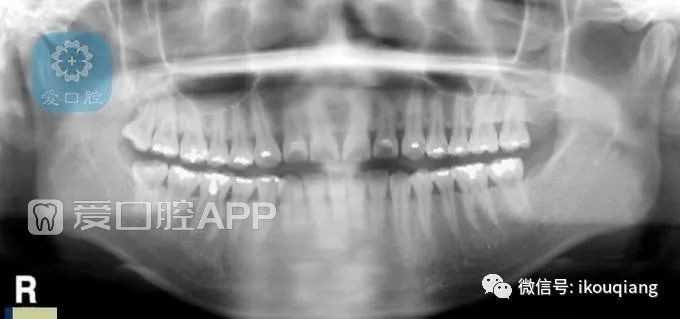

▲图1 正常曲面断层的影像的四个基本条件显示

正常曲面断层的影像的四个基本条件显示(见图1)

a、正中矢状线

b、微笑的咬合曲线

c、两侧髁突应在同一水平

d、臼齿显示是正常的